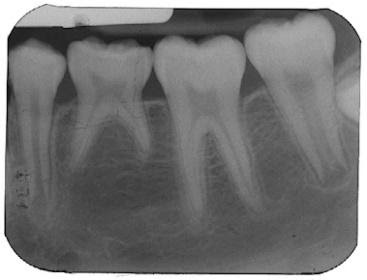

Khoảng 6 tuổi trẻ sẽ mọc răng hàm lớn vĩnh viễn đầu tiên – răng số 6, đây là chiếc răng ví như chìa khóa khớp cắn của hàm răng vĩnh viễn, bất cứ sự sai lệch nào về vị trí răng 6, cũng như bệnh lý của chiếc răng này đều ảnh hưởng đến toàn bộ hàm răng vĩnh viễn. Mà sự mọc ngay ngắn răng số 6 là mục tiêu chính của các hàm giữ khoảng chức năng hiện tại.

Nếu trẻ mất răng sớm thì răng số 6 sẽ có xu hướng di chuyển về phía gần hay phía trước khi đó nó sẽ chiếm chỗ, làm mất khoảng của các răng vĩnh viễn khác mọc sau, gây nên tình trạng chen chúc ở hàm răng vĩnh viễn đồng thời thay đổi tương quan giữa răng số 6 trên và dưới tạo nên một khớp cắn sai và không ổn định